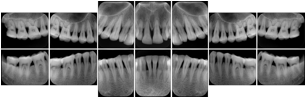

3. A patient in rural Minnesota experiences sudden vision loss and goes to a general ophthalmologist, who acquires OCT images and forwards them electronically along with a Structured Display to a retina specialist six travel hours away. The retina specialist is able to view the images in the standard layout that he is comfortable with, and to confirm that the patient has a choroidal neovascular membrane. He determines that is would be worthwhile for the patient to travel for treatment.

OCT Retinal Study with Cross Section and Navigation Structured Display

Figure OO-4. OCT Retinal Study with Cross Section and Navigation Structured Display